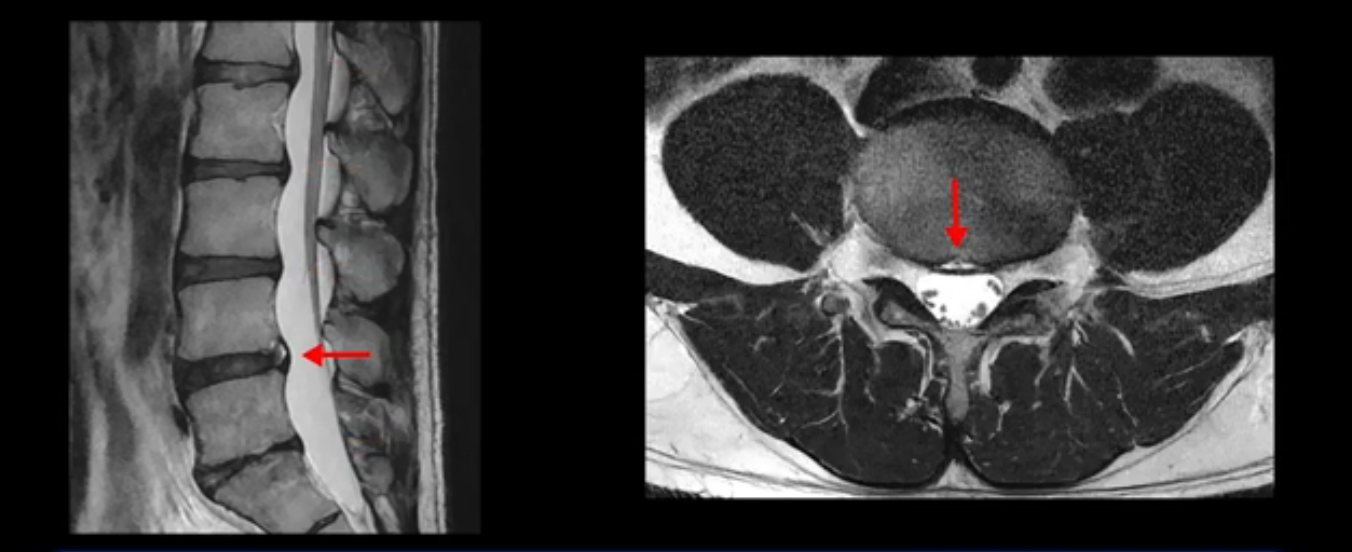

4번 5번은 가운데로 섬유륜이 찢어져서 디스크가 살짝 밀려나와 있지만 역시나 최근에 찢어지고 밀려나온 걸로 판단되지 않고 오래 전에 찢어진 흔적으로 보입니다.

이분은 어떤 한 병원에서 디스크 내장증 얘기를 들으셨는데요. 여기 보시는 것처럼 4번 5번의 하얀 HIZ(High Intensity Zone)을 보고 디스크 내장증의 근거로 얘기하는 병원들이 있는데,

이 HIZ는 섬유륜이 찢어졌다가 이미 아문 뒤에도 얼마든지 보일 수 있는 흔적일 가능성이 있어서 재채기를 하면 아픈지, 허리를 구부릴 때 날카로운 통증이 생기는가 등의 증상으로 구별해야 하는데 MRI만 보고 HIZ가 보이면 그게 마치 통증의 원인인 것처럼 얘기하는 의사들이 있습니다. 이분 MRI를 자세히 보고 증상을 정말 자세히 들어본 의사가 있었더라면 다른 환자분들처럼 증상과 MRI가 일치하지 않는다는 얘기를 들을 수 있었을 텐데 이분은 그런 얘기는 듣지 못했습니다.